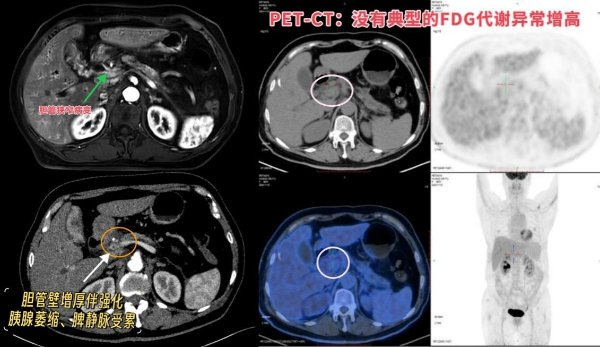

隔天,何阿姨就接受了PET-CT检查——这是用于肿瘤诊断和分期重要的先进手段,是明确患者病情的“好武器”。然而,结果不仅没有清晰,反而变得更加让人困惑。

PET-CT结果显示:何阿姨胆管下段管壁增厚、FDG不均匀增高,考虑炎症病变、肿瘤不能排除;腹腔淋巴结炎性增生可能大。

反复推敲患者检查结果后,核医学科主任陈涛对治疗团队表示,“如果是恶性的,那当然要准备十二指肠切除术(Whipple术),但是这种手术围手术期死亡率5%-10%,风险你们肯定比我更清楚;万一最后病理查下来结果是良性……一定要三思、慎重!”